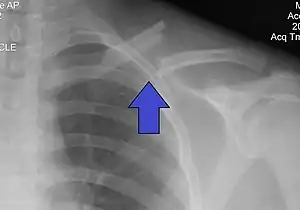

X-ray of a left clavicle fracture

The basic method to check for a clavicle fracture is by an X-ray of the clavicle to determine the fracture type and extent of injury. In former times, X-rays were taken of both clavicle bones for comparison purposes. Due to the curved shape in a tilted plane X-rays are typically oriented with ~15° upwards facing tilt from the front. In more severe cases, a computerized tomography (CT) or magnetic resonance imaging (MRI) scan is taken. However, the standard method of diagnosis through ultrasound imaging performed in the emergency room may be equally accurate in children.[5]